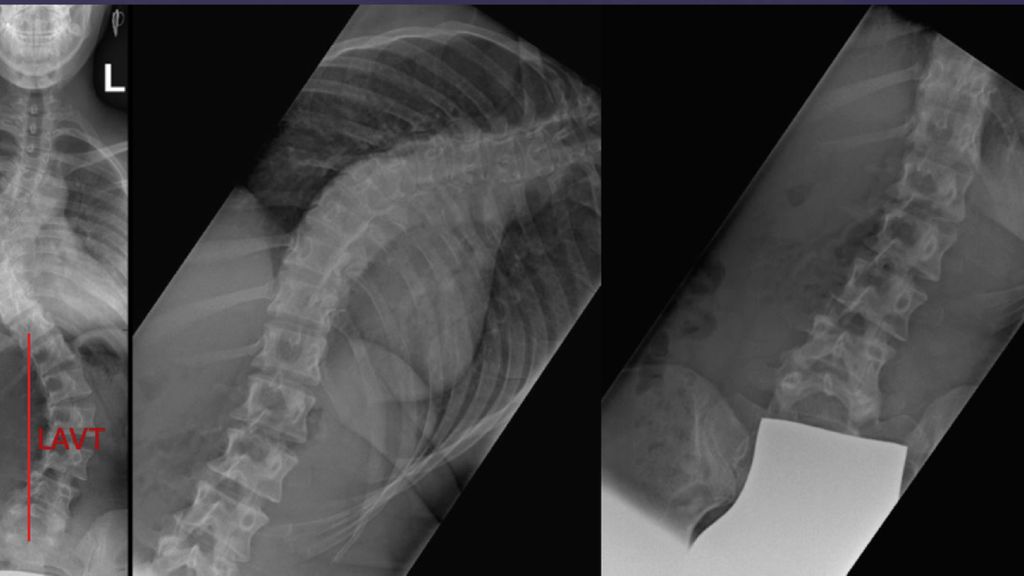

Typischerweise korrigiert eine lumbale kompensatorische Krümmung im Gegensatz zu einer strukturellen in der Bending-Aufnahme unter 25° und weist eine geringe lumbale apikale vertebrale Translation (LAVT) auf. Daher ist die Durchführung einer korrekten Bending-Aufnahme, die Seitneigung nach links und rechts in der Frontalebene im Rahmen der präoperativen Planung, essenziell (Abb. 1). Während die Hauptbewegung von Halswirbel und Lendenwirbelsäule durchgeführt wird, ist die Brustwirbelsäule durch Rippen und Sternum fixiert und weist daher von Natur aus eine geringe „range of motion“ (ROM) aus.

Abb. 1: a) Sportlich sehr aktive Patientin mit Lenke-3C-Skoliose mit niedrigem LAVT, lumbales Bending < 25°; b) unmittelbar postoperatives Ergebnis nach selektiver thorakaler Fusion bis Th 12, die vollständige mobile Lendenwirbelsäule konnte erhalten werden